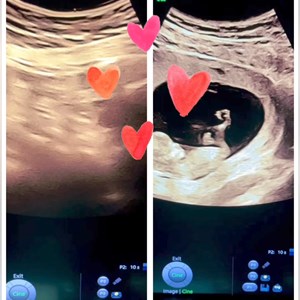

Ét af mandagens besøg 🫶🩷 Sød lille pige. 15 uger og kampvægt på ca 120 gram. Hun er så ...